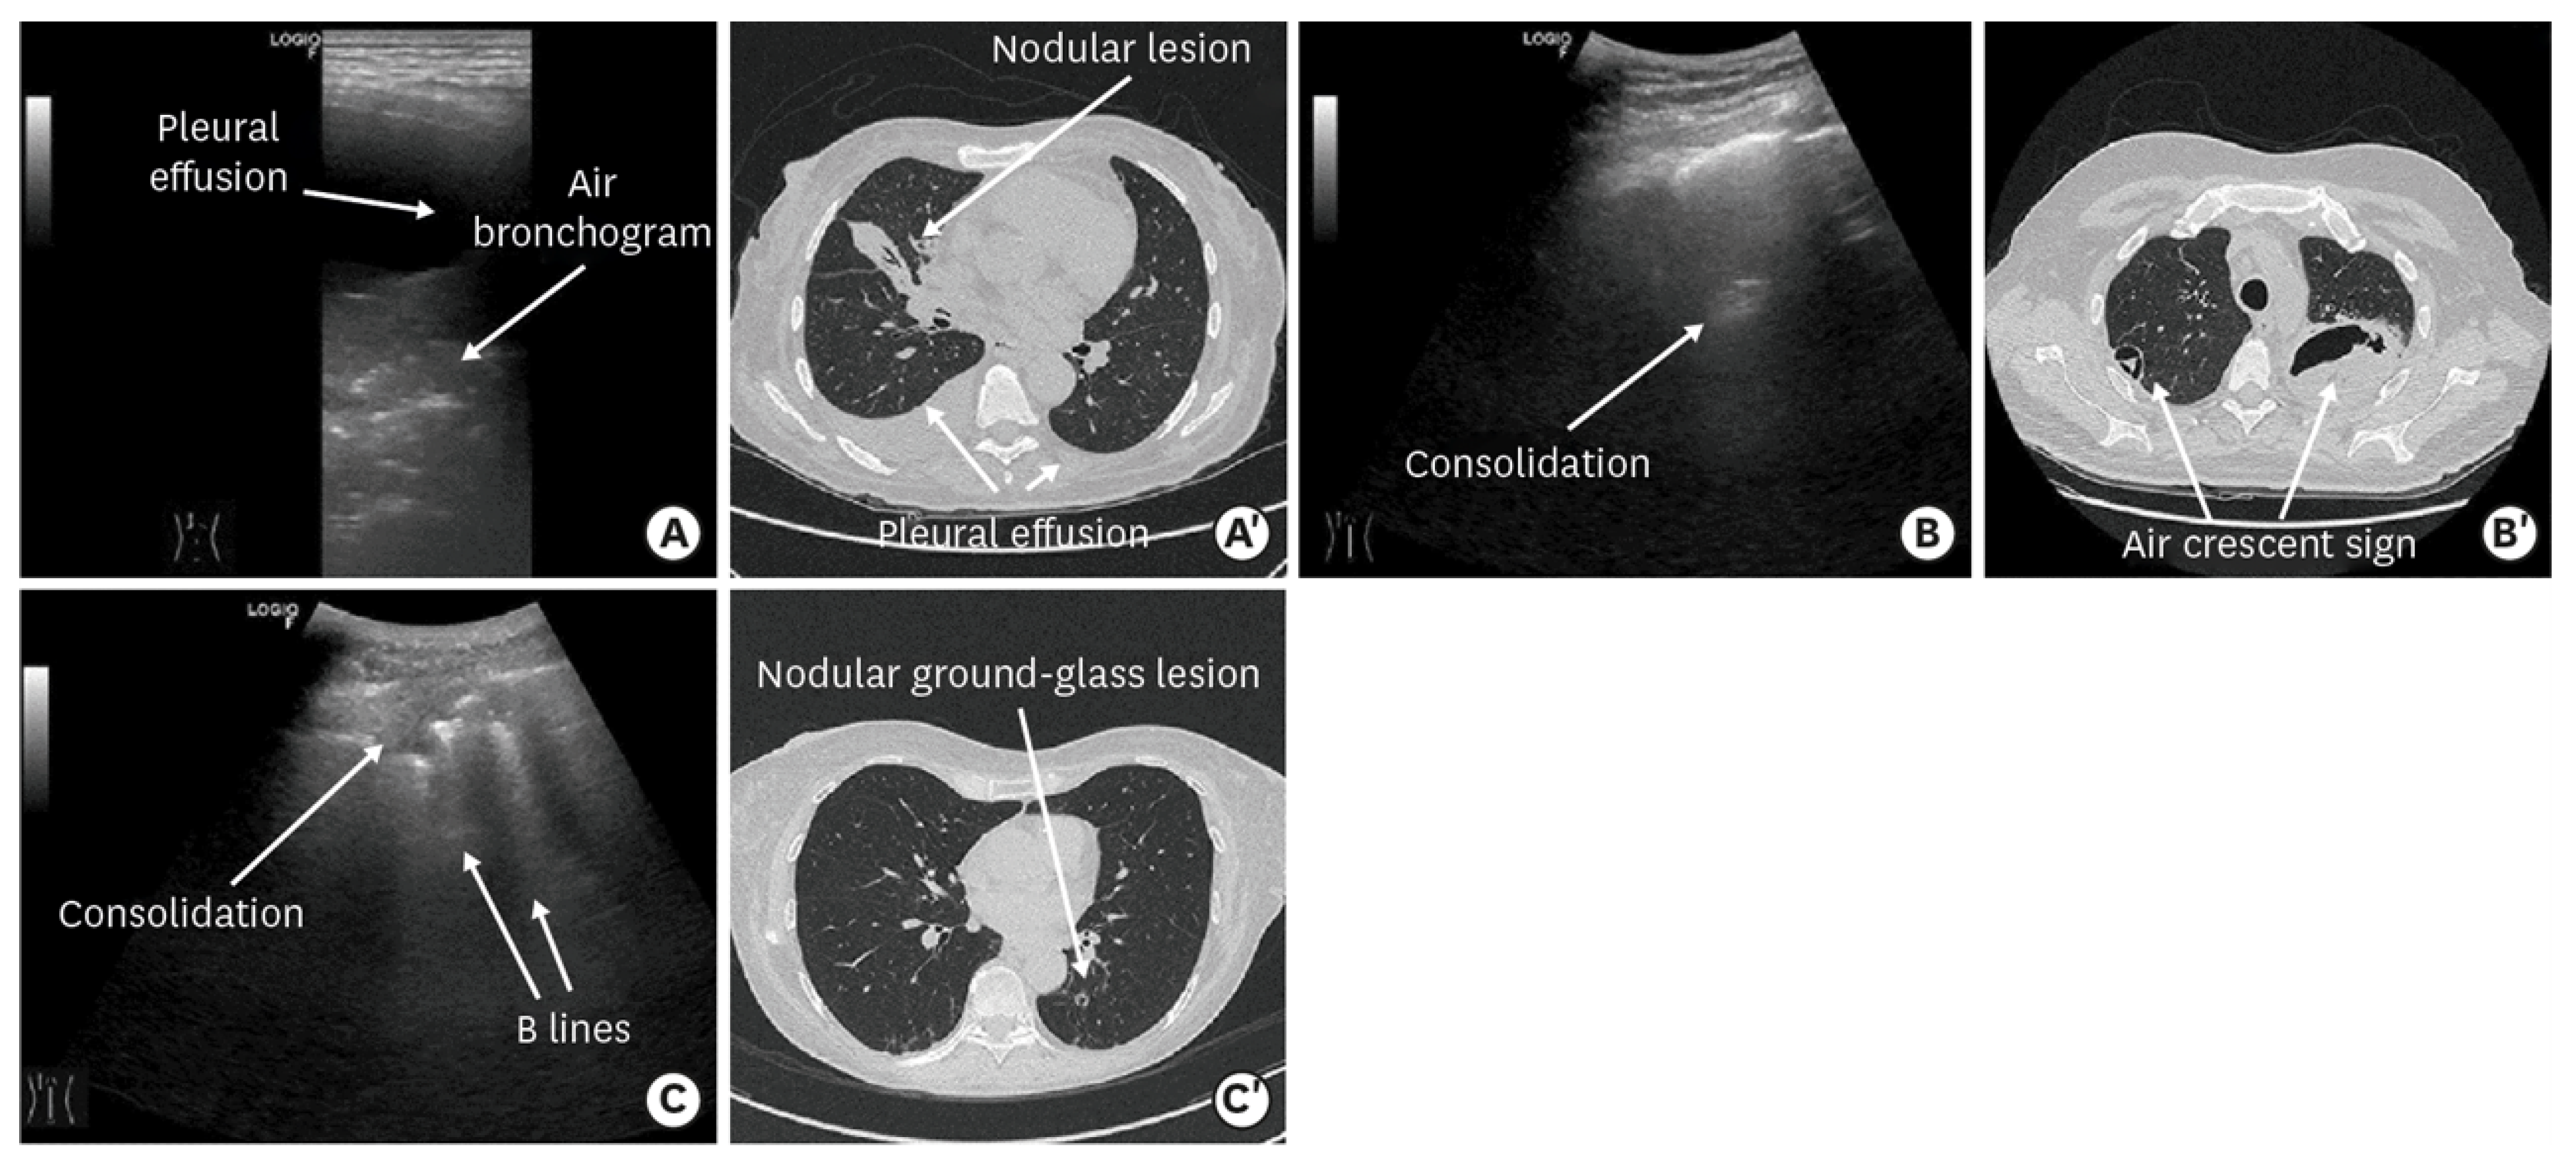

3.2.1. Intracellular Pathogens Lung Infection

3.2.2. Fungal Lung infection

3.2.3. Mycobacterium tuberculosis Lung Infection

4.3. Fungal Lung Infection

| Consolidation | Area in which lung tissue is de-aerated with density similar to parenchymal tissues [23] |

| Atelectasis | Type of consolidation shown as hyperechogenic tissue structure visualized as solid parenchyma with static air bronchogram [11,24] |

| Cavitation | Solid, hypoechoic, heterogeneous lesions with sharp lobulated margins [11,25] |

| Pleural effusion | Hypo- or anechogenic structure, delineated by the chest wall and the diaphragm [11,26] |

| B-lines | Vertical reverberation artefacts from the pleural line to the edge of the scree; laserlike, vertical hyperechogenic artefacts synchronized with pleural line [11,23,27] |

| Pleural irregularities | Reduction or interruption of pleural line [11,28] |

| Sub-pleural nodes/granularities | Hyperechogenic subcentimetric granularities or consolidation under the pleural line [29,30] |